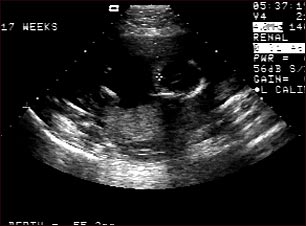

Ultrasonido de un feto normal; ventrículos cerebrales

Ultrasonido normal a las 17 semanas de gestación. El cerebro y el sistema nervioso comienzan a desarrollarse con prontitud en la vida del feto. Al realizar un ultrasonido, el técnico por lo general busca la presencia de los ventrículos cerebrales, los cuales son los espacios llenos de líquido en el interior del cerebro. En este ultrasonido los ventrículos pueden observarse en la parte superior derecha en forma de líneas finas que se extienden a través del cráneo. La cruz apunta hacia la parte frontal del cráneo y a su derecha se pueden observar las líneas de los ventrículos.